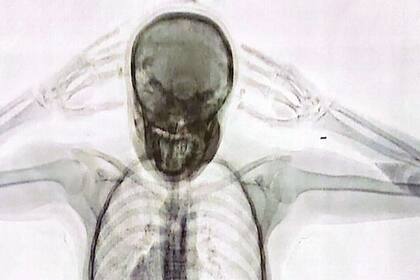

El operativo comenzó cuando el acusado se presentó para realizar el check in de un vuelo de Air France. Frente al estado de nerviosismo que presentaba el pasajero, el personal aduanero sospechó que algo ocultaba. Durante la entrevista, el ciudadano de Brasil no logró explicar el motivo del viaje ni quien había comprado el pasaje aéreo. Además, dado el trayecto que realizaba, los agentes pensaron que podría estar ocultando drogas. Ante todos los indicios, se inspeccionó su equipaje, pero no se encontró nada anormal. De todas formas, se decidió utilizar otro método de control: el body scan.

Las imágenes confirmaron las sospechas del personal aduanero dado que mostraban cuerpos extraños. En total eran 84 cápsulas que contenían 1134 gramos de cocaína que en el país de destino se podría vender a US$51.000.